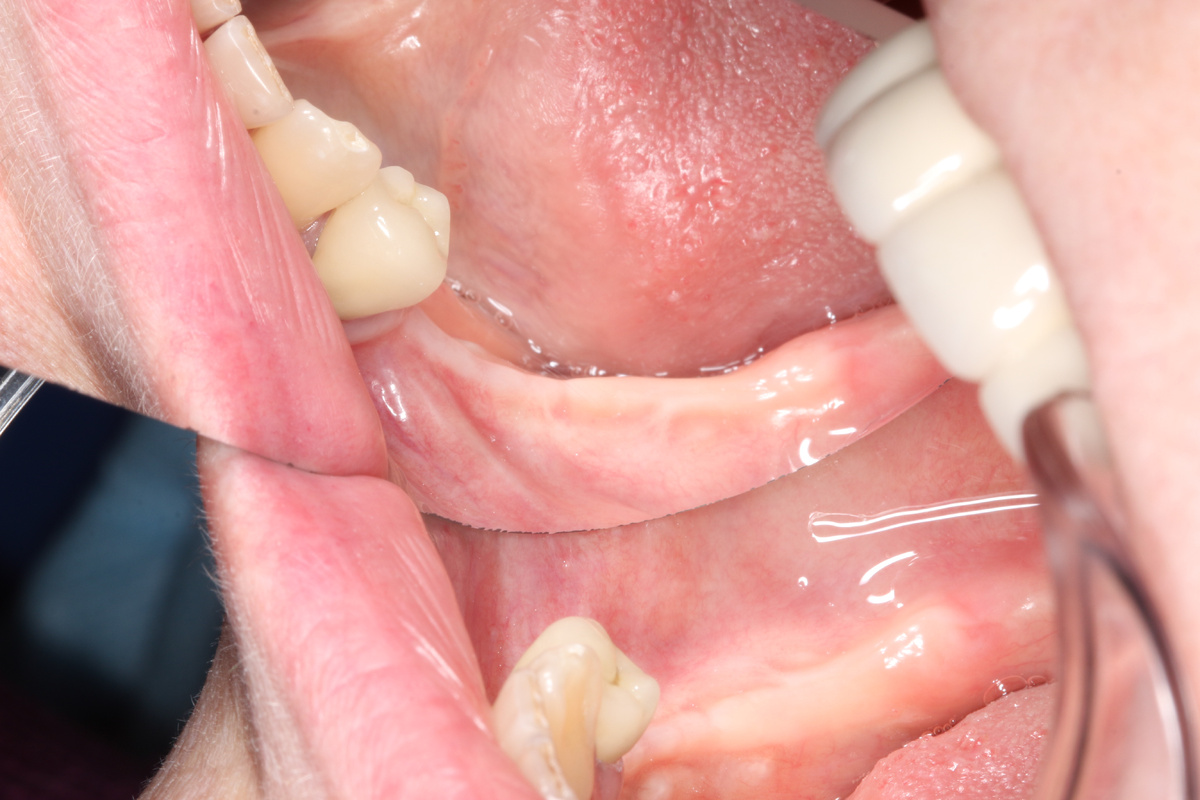

Пациентке в другой частной клинике провели костную пластику на нижней челюсти в области жевательных зубов. Через год мы выполнили установку двух имплантов. Импланты прижились, но тонкая слизистая не позволяла начать протезирование. Поэтому приступили к пластике десны.

Сохранена тонкая полоска плотной десны на вершине, дальше – тяжи слизистой.

I этап: проведен забор СДТ с неба. Слизистая с тяжами аккуратно отсечена, смещена вниз, где фиксирована швами. На освободившееся место пересажен СДТ.

Ситуация через 4 недели.

Получена широкая зона плотной десны после приживления трансплантата. Однако ей не хватало объема для противостояния комку пищи, что редко получается достичь пересадкой СДТ.

II этап: в день установки формирователей десны подсажен ССТ, взятый с бугра верхней челюсти.

Вот такой результат еще через 4 недели:

Такому объему плотной и неподвижной слизистой не страшна самая твердая пища. Хорошо и для гигиены: при чистке щеткой десна не будет кровоточить и травмироваться. Комфорт и удовольствие, надежность и стабильность обеспечены.